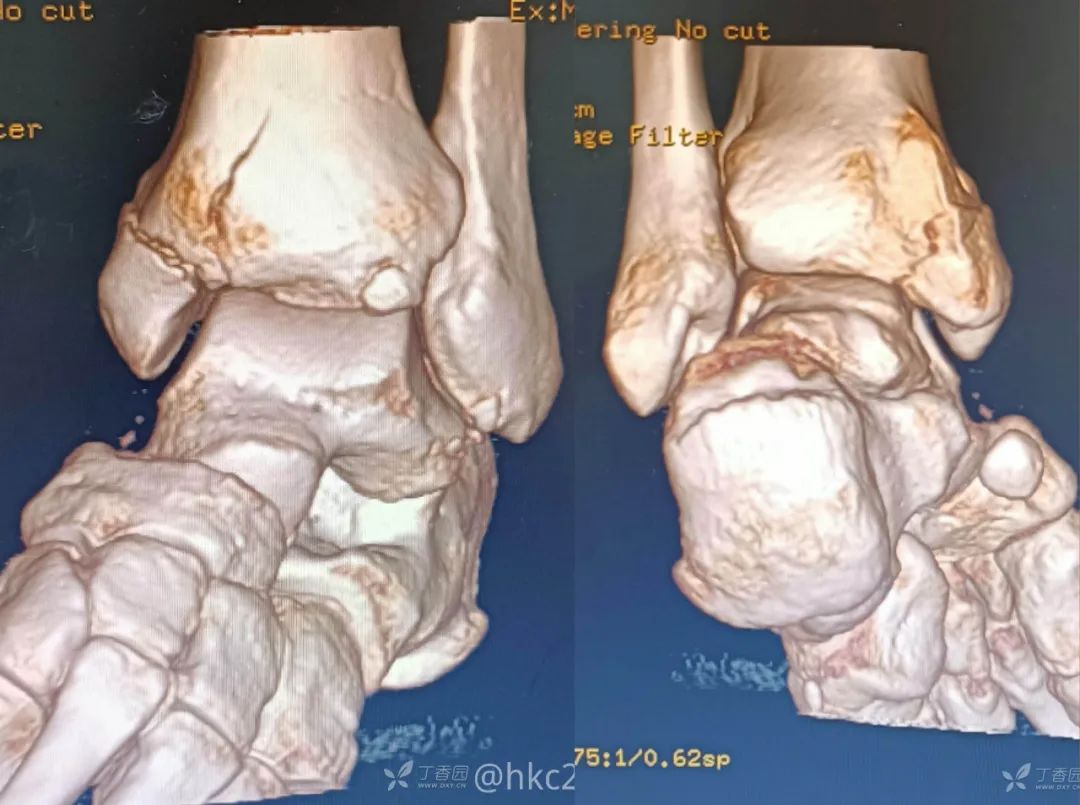

这是一例三踝骨折的患者。

距腓前韧带距骨侧和腓骨侧双束断裂

踝关节严重不稳